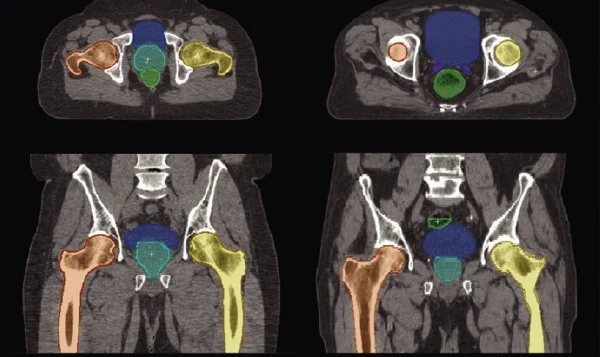

A machine learning tool to analyse patient scans and speed up preparation for radiotherapy treatment.